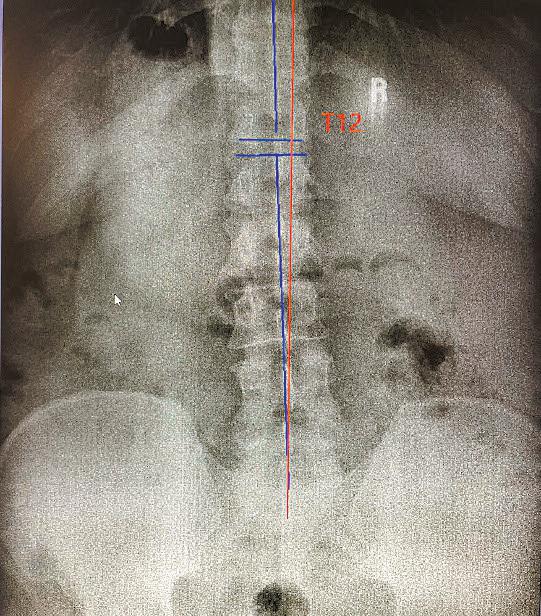

The nervous system controls and coordinates all functions of the body, making its proper functioning essential for overall health. Structural shifts in the spine can obstruct the nerves and interfere with their function. Chiropractors refer to these obstructions as vertebral subluxations, and they are at the core of chiropractic care.

Find out if subluxations are affecting your health with a chiropractic examination with any necessary x-rays for just $59 this month at any Crossroads Chiropractic location.

For over 23 years people have come to us for help with: Sciatica Neck Pain Low Back Pain

$59 complete exam Call (603)575-9080 to schedule! with x-rays, if necessary

Digestive Problems Asthma Colic Enhanced Performance Headaches and Migraines Chronic Ear Infection Numbness/ Tingling in Hands ADD/ADHD Overall Wellness *results

MEREDITHPEMBROKE EPPING BEDFORD Crossroads Chiropractic For adult health and pediatric development